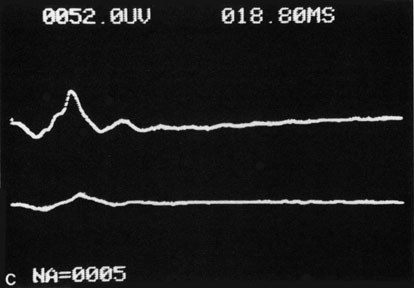

Hypoperfusion retinopathy is characterized by dot and blot hemorrhages in the midperiphery of the fundus, by venous tortuosity and engorgement, by microaneurysms, and by the occasional sludging of blood within the veins. Fluorescein angiography may show areas of capillary nonperfusion; it may also show microaneurysms in the midperiphery and slow arm to retina or arteriovenous transit time (Fig. 9A and 9B).174 The condition does not usually affect the posterior pole, and patients typically have normal visual acuity, although an occasional patient may have macular edema.174 The entire periphery of the eye is usually affected, although there may be more hemorrhages in one quadrant than another. Patients occasionally experience ocular discomfort or eye pain despite normal intraocular pressure. Reduction of the ophthalmic arterial pressure is a pathognomonic feature. Disc edema and disc collaterals are generally not present. The electroretinogram shows abnormalities in both the a- and b-waves (see Fig. 9C).

Fig. 9. Intravenous fluorescein angiogram of a patient with hypotensive or hypoperfusion retinopathy. A: There is a marked delay in the choroidal and retinal filling. B: In the recirculation of the angiogram, there is a characteristic staining of both arteries and veins. C: Electroretinogram shows normal a- and b-waves in the normal right eye (upper tracing) and marked redirection of the a- and b-waves in the affected left eye (lower tracing).

Histopathologic examination of eyes with hypotensive retinopathy demonstrates intraretinal hemorrhages and numerous microaneurysms, particularly in the midperiphery and periphery, and a decrease of the pericyte to endothelial cell ratio.175 The ophthalmoscopic appearance and effect on the retina and optic nerve has been reproduced in an animal model using mature rats after carotid artery ligation176,177,447–451. Unilateral carotid artery ligation has produced inconsistent and less severe changes.176 Symptoms do not occur until the blood flow in the carotid artery distal to a stenosis is reduced, which is only when the stenosis is more than 60% to 65%.177